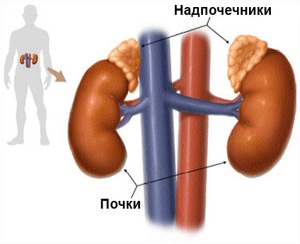

Ultrasunete glandele suprarenale - una dintre aceste studii scopul de a evalua starea glandelor suprarenale, care sunt situate la polul superior al ambilor rinichi și de a efectua o functie foarte importanta endocrine la om. Ultrasunete a rinichilor și a glandelor suprarenale adesea efectuate simultan.

suprarenale

glandele suprarenale - un organ pereche endocrin

Suprarenale - un organ pereche endocrine reprezentând o glanda, constând din două părți - și cortexul cerebral. Fiecare dintre aceste straturi îndeplinește funcțiile sale prin secretarea de hormoni diferite.